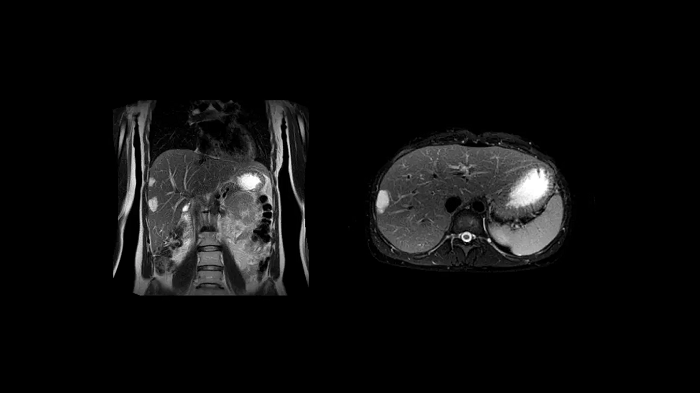

T1 VIBE Dixon with CAIPIRINHA

Benefit from Siemens Healthineers’ dedicated CAIPIRINHA acceleration to gain a complete abdominal volume within a single breath-hold. The Dixon technique offers outstanding fat-water separation for a flawless representation of the abdominal anatomy.

- Contour L Coil

- Spine Coil

Image Courtesy: University Hospital Erlangen, Germany | Image-ID: 4aaaa0458